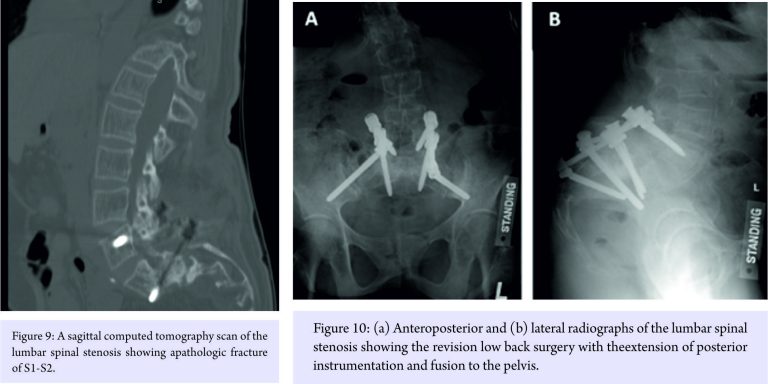

She later developed a pathologic (osteoporotic) fracture S1-S2 (Fig. 9) for which posterior instrumentation was revised with the extension of fusion to the pelvis (Fig. 10).